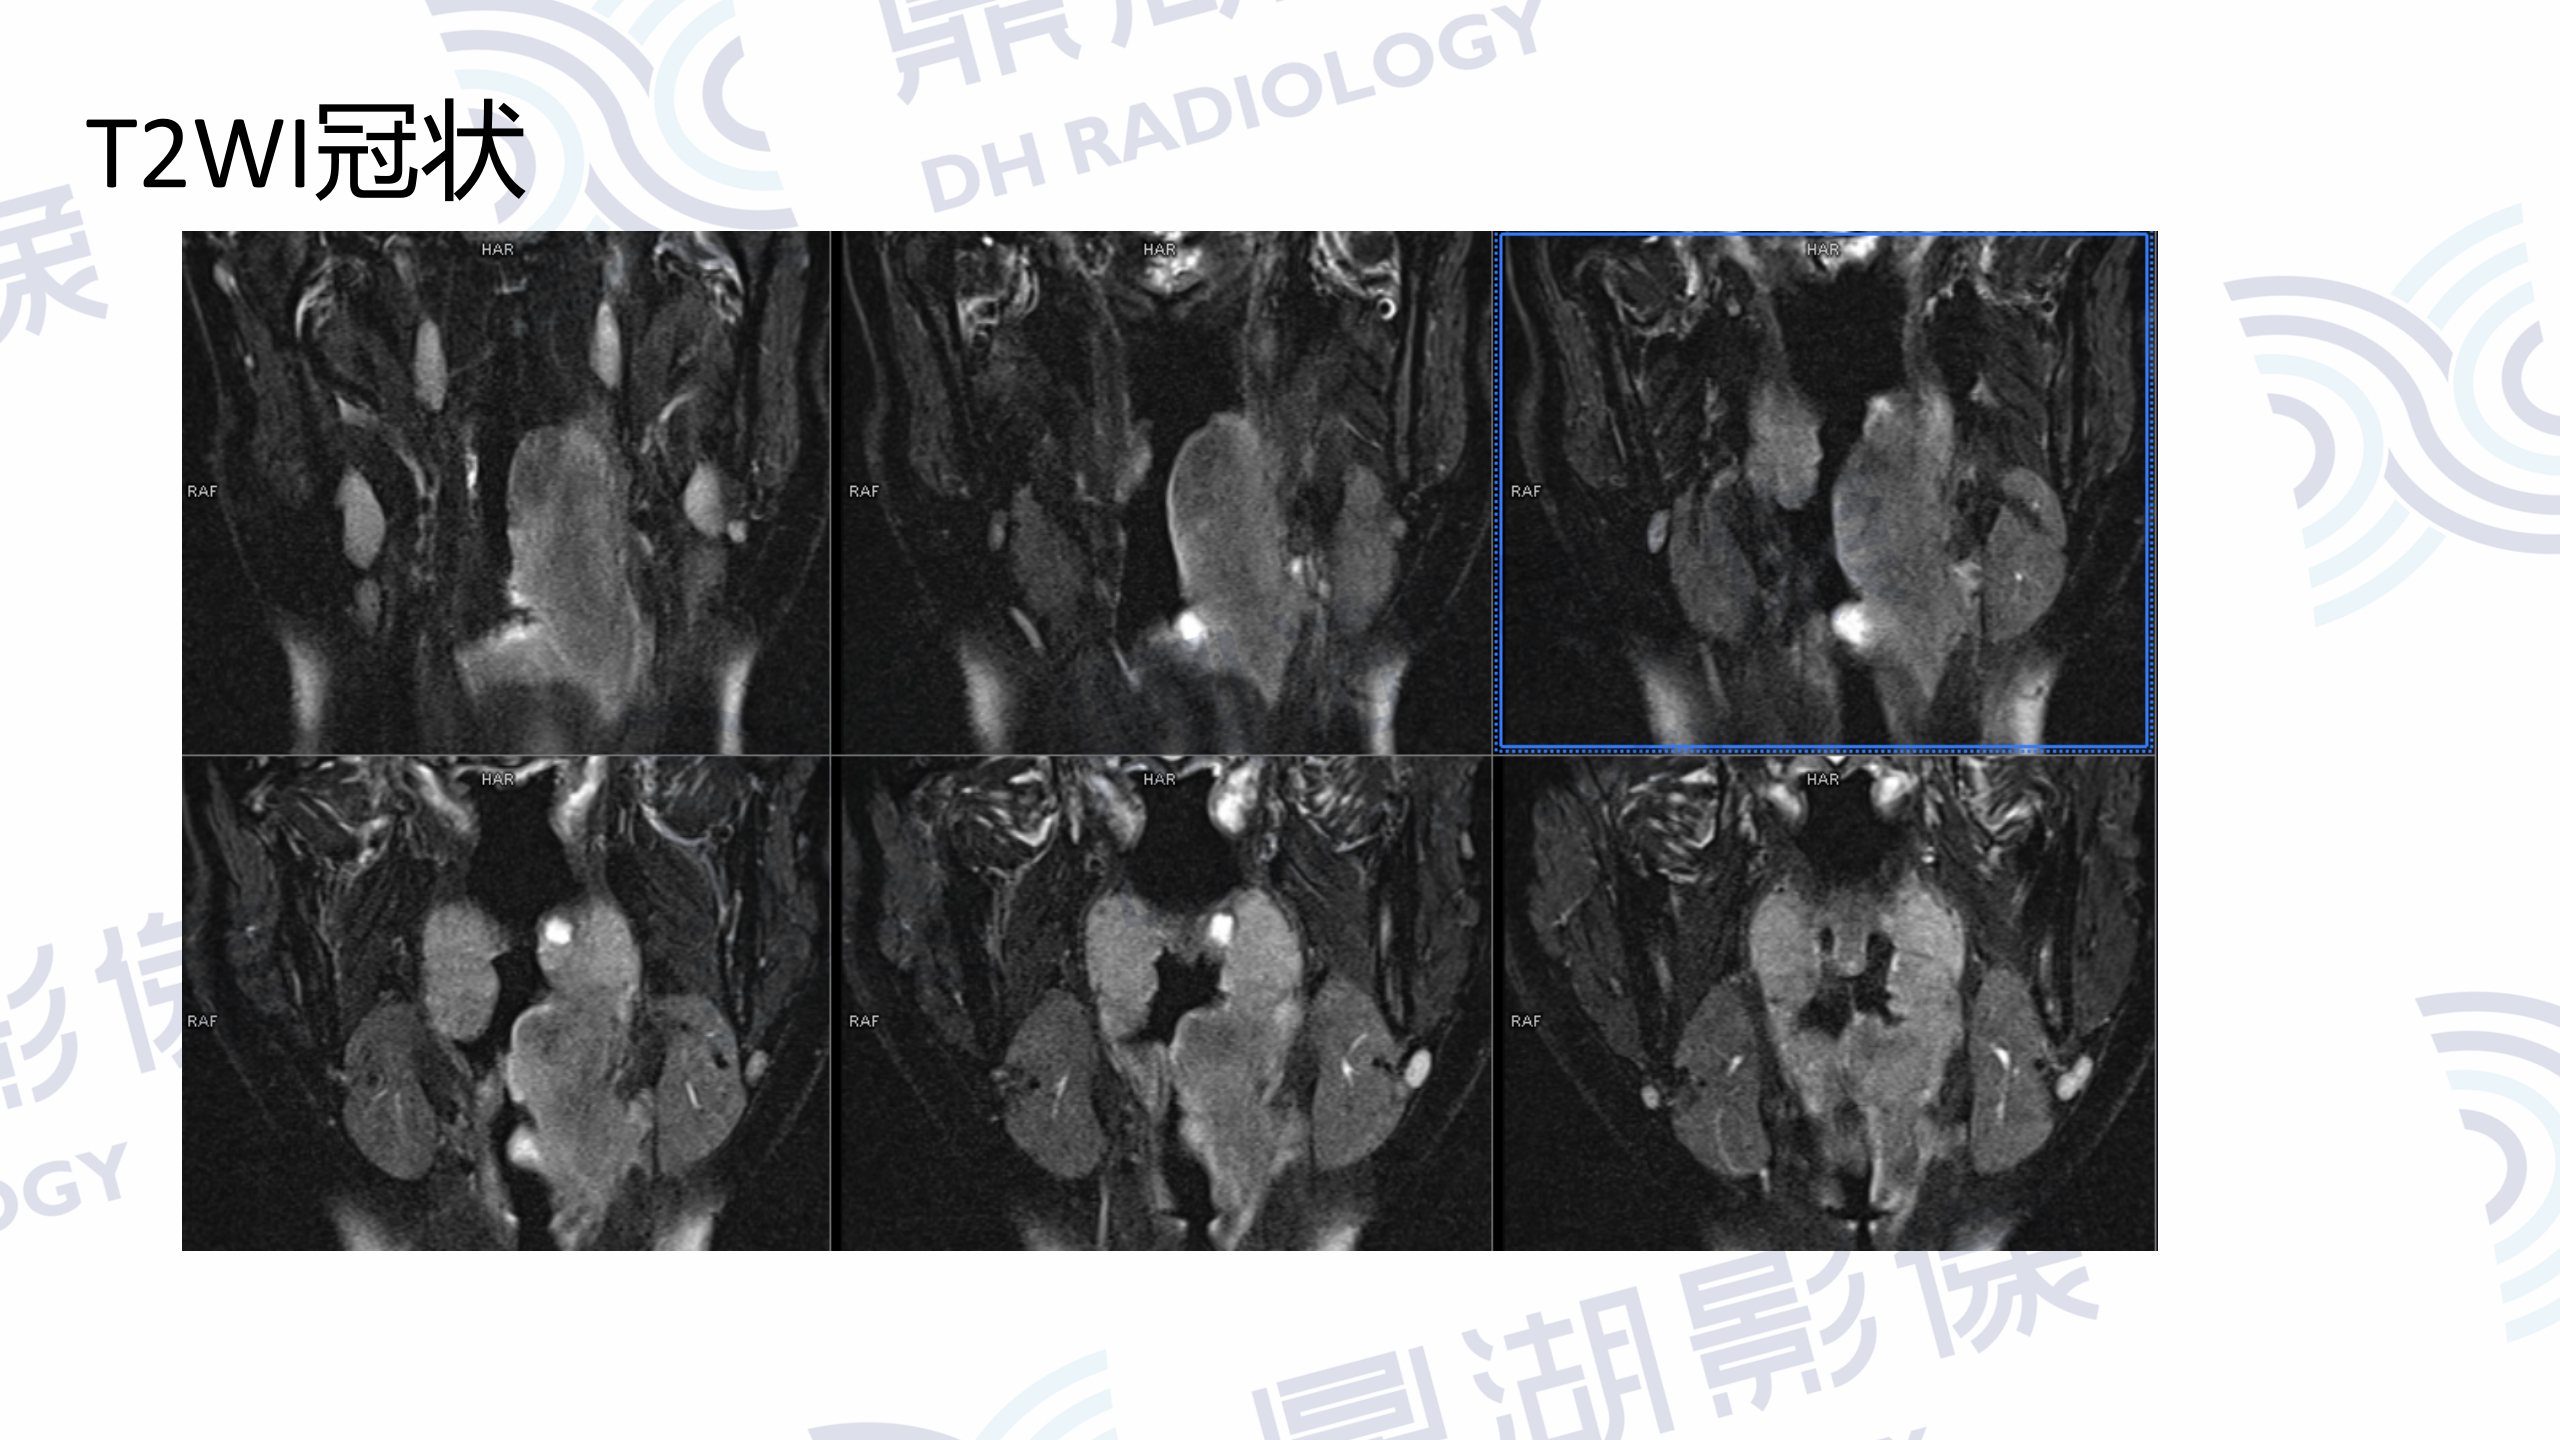

MR增强检查提示:口咽左侧壁至左侧声门上不规则软组织肿块,病灶突入咽腔,信号均匀,T1WI呈等信号,T2W呈稍高信号,DWI呈高信号,增强扫描呈轻度均匀强化,左侧杓状会厌皱襞水肿,左侧梨状窝消失。

口咽部活检病理为淋巴组织增生,IgG4浆细胞浸润阳性。